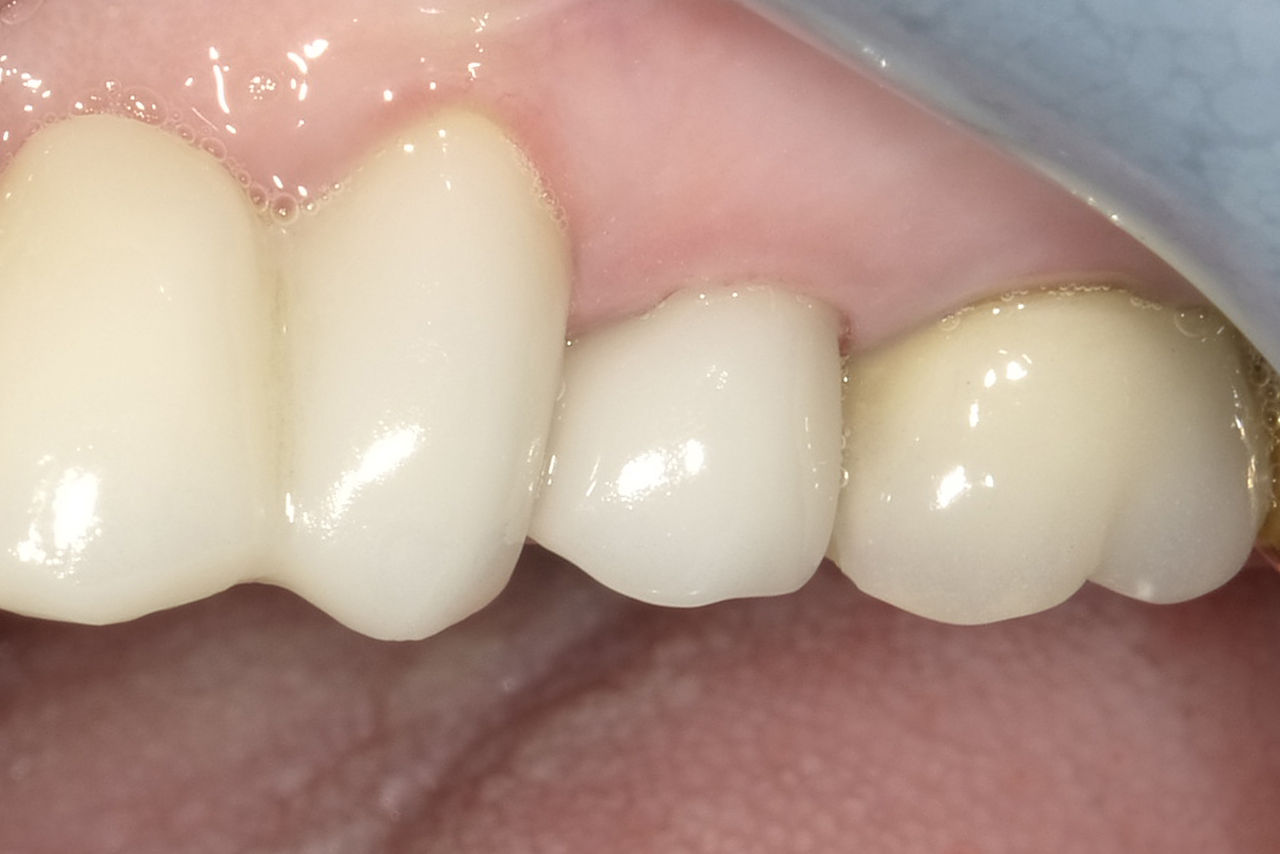

Primer premolar superior en 90 minutos

Colocación de implante Ankylos y de una corona individual IPS.emax CAD

En un plazo de 90 minutos, se produjeron y colocaron las prótesis finales después de un tratamiento de implante, gracias al flujo de trabajo chairside digital con CEREC. El paciente estaba muy satisfecho con eso.

Antes: Diente 24 con fractura horizontal de raíz e infección periférica.

Después: Preservación de la estética y del contorno natural de los tejidos blandos.